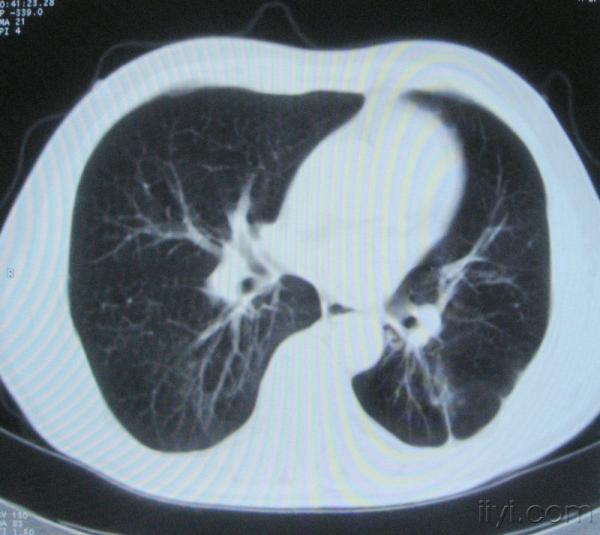

男。60岁,胸片示支气管炎治疗后复查CT。

你指那个肯定是淋巴结,中央系坏死,这很常见,特别在双侧腹股沟会经常看到。这个双侧腋窝及纵隔见多发小淋巴结征。

根据位置考虑应该是淋巴结,密度不均,是因为肿大的淋巴结中心液化坏死